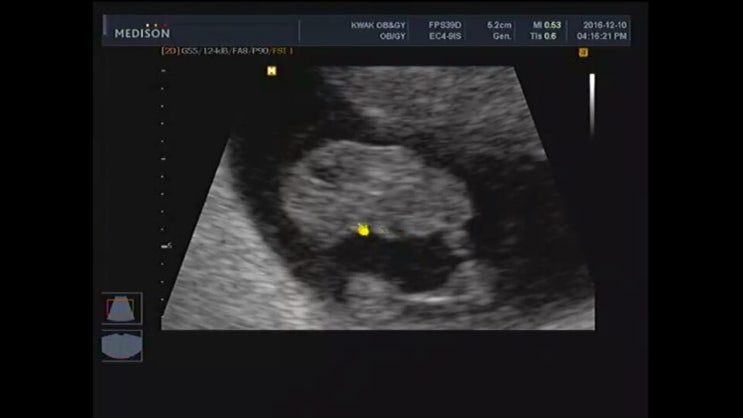

[임신 6주] 신혼 3년 차, 비단이를 만나다

16년도에는 내게 유독 많은 일들이 있었다. 직장을 그만두었고, 3개월 휴식 끝에 다니던 회사를 다시 복직...

[임신 8주] 젤리 곰 같은 너